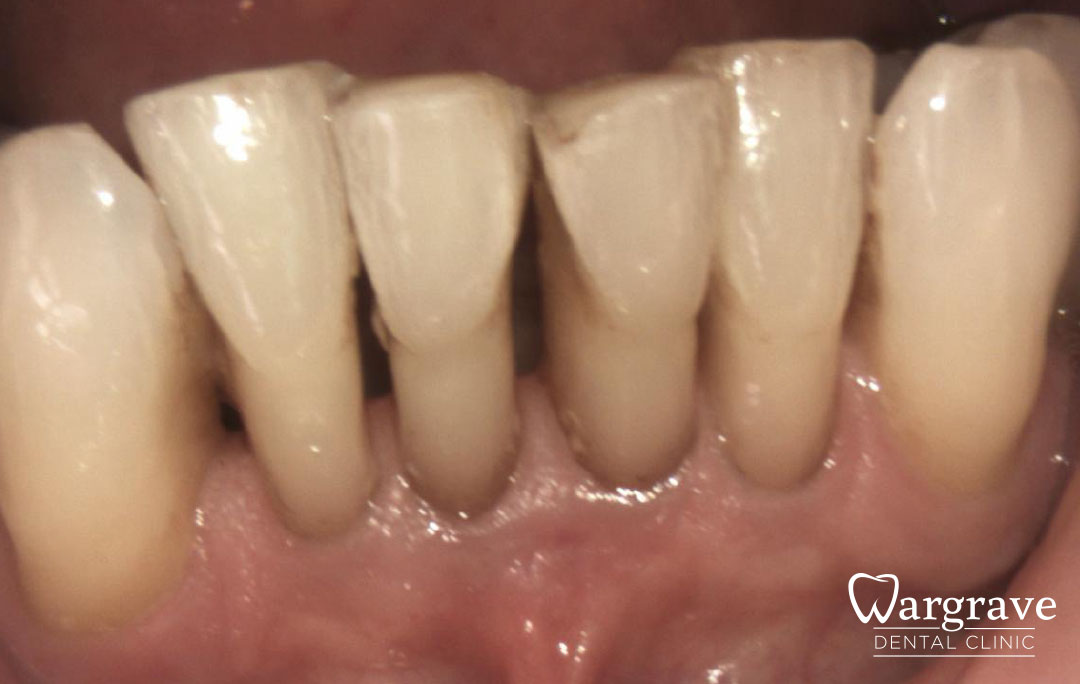

Healthy Smiles These are more advanced examples of different treatments available.All cases shown were carried out by Dr R Khurana unless otherwise stated. Immediate implants Anterior Mandible Bone Regeneration Anterior Mandibular Implant Bridge Maxillary Anterior Implant Bridge Implant stabilised ‘Life Like’ replacement dentures Implant Bridge after 10-years with zero bone loss Implant examples including ZBLC concepts Adhesive Bridge solution for a missing premolar Multidisciplinary care Orthodontics, Replacement veneers and composite bonding Adhesive Bridge solution for missing central incisors Replacement crown, Veneer and Composite Bonding Replacement Crowns and Veneer Injection Moulding using Composite Resin Equilibration Tooth Whitening to treat Developmental Discolouration